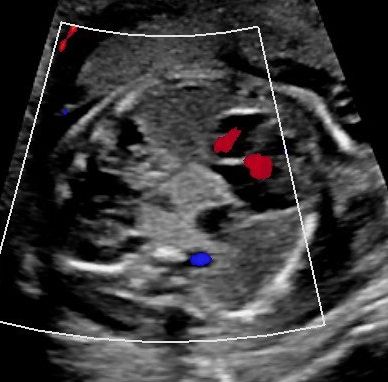

Sonoanatomie, Biometrie, Hinweiszeichen & Diagnose von Entwicklungsstörungen, Kasuistiken, ausreichend Zeit für Diskussionen, Fallbeispiele aus der Praxis (Quiz)